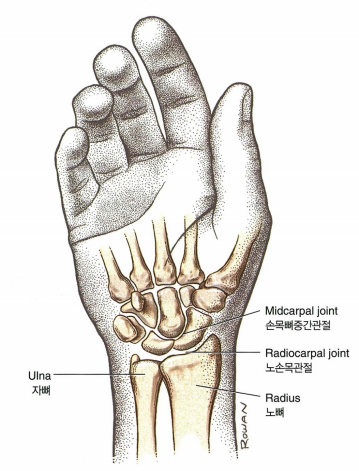

2. 해부학

- 손목에 작은 뼈들은 8개로 구성되어있습니다.

- 근위열 4개뼈

- 주상골(scaphoid), 월상골(Lunate), 삼각골(Triquetrum), 두상골(Pisiform)

- 원위열 4개뼈

- 대능형골(Trapezium), 소능형골(Trapezoid), 유두골(Capitate), 유구골(Hamate)

- 근위열 4개뼈